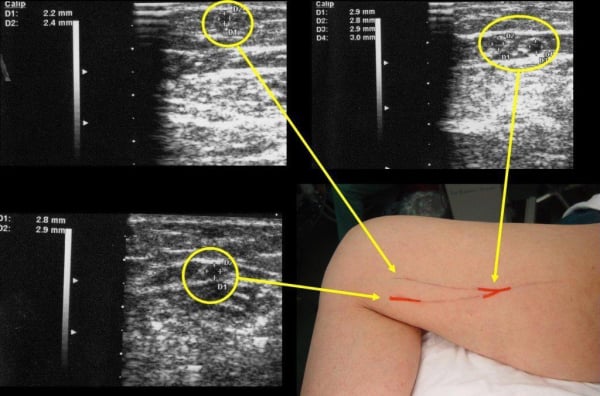

Doppler Αγγείων – Σφυροβραχιόνιος Αρτηριακός Δείκτης Πίεσης (ABPI)

Ο ABPI είναι χρήσιμος για την αξιολόγηση της περιφερικής αρτηριακής ανεπάρκειας.